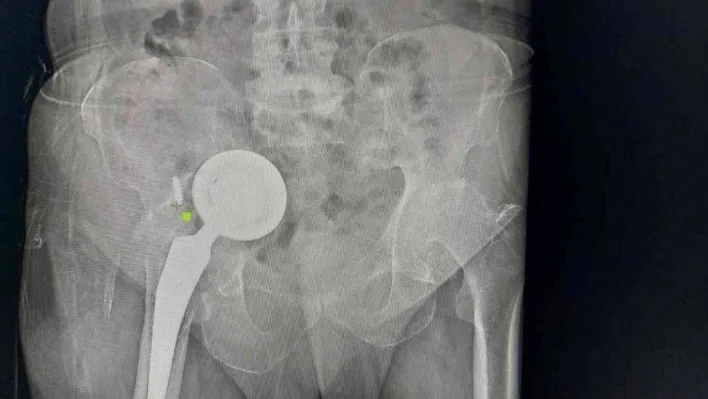

Adıyaman’da yaşayan 74 yaşındaki Ömer Demir, geçtiğimiz yıllarda kalça bölgesinde hissettiği rahatsızlıklar sonrası doktora gitti. Kalçasında kireçlenme olduğu belirlenen Demir, kalça protezi ameliyatıyla şikayetlerinden kurtuldu. Edinilen bilgiye göre zaman içerisinde yeniden ağrılar hissederek hastaneye başvuran Demir’in protezine revizyon ameliyatı yapıldı. Ancak bir süre sonra yaşlı adamın ağrıları yeniden kendini gösterdi ve uzmanlar operasyon gerekliliğini ifade etti. İddiaya göre geçirdiği operasyonlar sonrası tekrar ameliyat olmak istemeyen Demir, gittiği birçok doktoru dinlemedi, protezi ise karın içi ve uyluk kemiğinde ilerlemeye başladı. Zamanla ağrıları dayanılmaz hale gelen yaşlı adam, en son Başakşehir Çam ve Sakura Şehir Hastanesi’ne geldi. Burada yapılan tetkikler sonrası protezin diğer organlarını olumsuz etkileyecek şekilde vücudunda ilerlediğini duyan yaşlı adam, ameliyata onay verince acil şekilde operasyona alındı. Başakşehir Çam ve Sakura Şehir Hastanesi Ortopedi ve Travmatoloji Uzmanları Dr. Mustafa Özçamdallı ve Dr. Necati Doğan’ın ekipleriyle gerçekleştirdiği operasyonla protezin üst kısmı karın içinden alt kısmı ise hastanın bacağından çıkarıldı. Yeni protez ise başarılı bir şekilde bölgeye yerleştirildi. Hastada yaşanan durumla çok sık karşılaşmadıklarını ifade eden Uzm. Dr. Özçamdallı ve Doğan tedaviye ilişkin bilgi verirken Demir, yaşadıklarını anlattı.

Demir’in geldiği pozisyonu ve uyguladıkları tedaviyi anlatan Dr. Necati Doğan, “Hastamıza yıllar önce kalça kireçlenmesi nedeniyle kalça protezi uygulanmış, bu protez uygulamalarında sıklıkla başarılı sonuçlar elde ederiz. Daha önce gittiği hastanelerde bu protezin yenilenmesi gerektiğini hastamıza söylemişler. Hastamız o anki risklerden dolayı bu süreci kabul etmemiş, ötelemiş ve yaklaşık 2-3 yıl boyunca bu protezi kullanmaya devam etmiş. Protezde ilerlemeye devam etmiş. Bize başvurduğunda artık protez karın içindeki organların arasına kadar yerleşmişti. Bacakta ciddi şişlikleri, hareket kısıtlılıkları oluşmuş, yürüyemez hale gelmişti. Yenileme ameliyatı gerektiğini söyledik ve hastamız artık mevcut tablosundan ileri derecede şikayetçi olduğu için belirli riskleri, ameliyatı kabul etti. Protezin bu kadar ileriye gitme aşaması sık karşılaştığımız bir şey değil, daha erken evrelerde geldiklerinde sadece kalça bölgesi açılır. Daha uyumlu protezlerle kalçadaki implant değiştirilir ve hayatına geri döner. Ama bu hastamız artık normal bölgeden çıkarılamayacak derecede ilerlemiş formuyla geldiği için bizim bu protezi kalça bölgesinden çıkarıp onarmamız imkansızdı. İlk olarak karın içindeki kısımları çıkartmak için karın bölgesinden girdik. Protezin yuva baş dediğimiz kısımlarını karın içinde mesanenin, bağırsakların, damar sinir paketlerinin arasından güvenli ve sorunsuz bir şekilde çıkarttık. Daha sonra bu kemikte oluşmuş ileri derecedeki defekti de onarmak gerekiyordu, buraya da uygun platinlerle tekrardan yeni yapılan protezler içeri gelmesin diye yeni platinlerle bir destek kısmı oluşturduk. Karın iç kısmındaki işimiz bitti daha sonra ikinci bir aşamada kalça bölgesinde kalan kısmı çıkarttık. Şu anki protezimiz gayet stabil ve hemen hareket etmeye, yük vermeye, yürümeye uygun bir protez. Vatandaşların protezlerini düzenli takip ettirmeleri gelişen herhangi bir yeni şiddetli ağrı ve problemlerde mutlaka en erken dönemde bu aşamalara gelmeden kontrollerini yaptırmalarını öneririm" dedi.

Protezin üst kısmının karın içinden alt kısmının ise bacaktan çıkarıldığını ifade eden Ortopedi ve Travmatoloji Uzmanı Dr. Mustafa Özçamdallı, “Hastamız bize geldiğinde yürüyemez bir vaziyetteydi daha önce birkaç kez operasyon geçirmiş ve protezi karın dediğimiz boşluğa kadar ulaşmış durumdaydı. Hastanın damarlarında ve sinirlerinde hasarlar meydana getirebilecek seviyedeydi. Özel dizayn edilmiş kafes dediğimiz protezlerle ve daha uzun revizyon dediğimiz protezlerle hastamızın operasyonunu başarılı şekilde gerçekleştirdik. Böyle durumlar hastaların ilerleyen dönemlerinde dolaşımını bozup bacaklarımı kaybetmeye kadar gidebilir. Bu hastamızda ek birtakım rahatsızlıklar olması sebebiyle diyabet, kalp rahatsızlığı, sebebiyle yatağa bağımlı olması bu hastalarda mortalite dediğimiz durumu arttırmaktadır. Bu çok sık karşılaştığımız bir hasta grubu değil. Kesinlikle kalça protezi yapılan hastalarımızın kontrollerine rutin olarak gitmeleri gerekir. Bu hastamız biraz operasyonlardan çekinmiş ve birkaç operasyona girince, çok yüksek olduğu anlatılınca korkmuş ve dolayısıyla bu şekilde hayatını bir 3-4 yıl daha idame ettirince protezin daha da aşınıp leğen kemiğinin yukarısına doğru çıkmasına sebep olmuş. Kendisine ameliyat önerilmesine rağmen ameliyatlarını kabul etmemişti ve bu protez leğen kemiğinde aşınmaya sebep olup karın içi organlara kadar ilerlemiş vaziyetteydi. Biz protezi 2 parça halinde çıkarttık. Protezin üst kısmını karın bölgesinden, alt kısmını uyluk kemiğinden çıkarttık" diye konuştu.